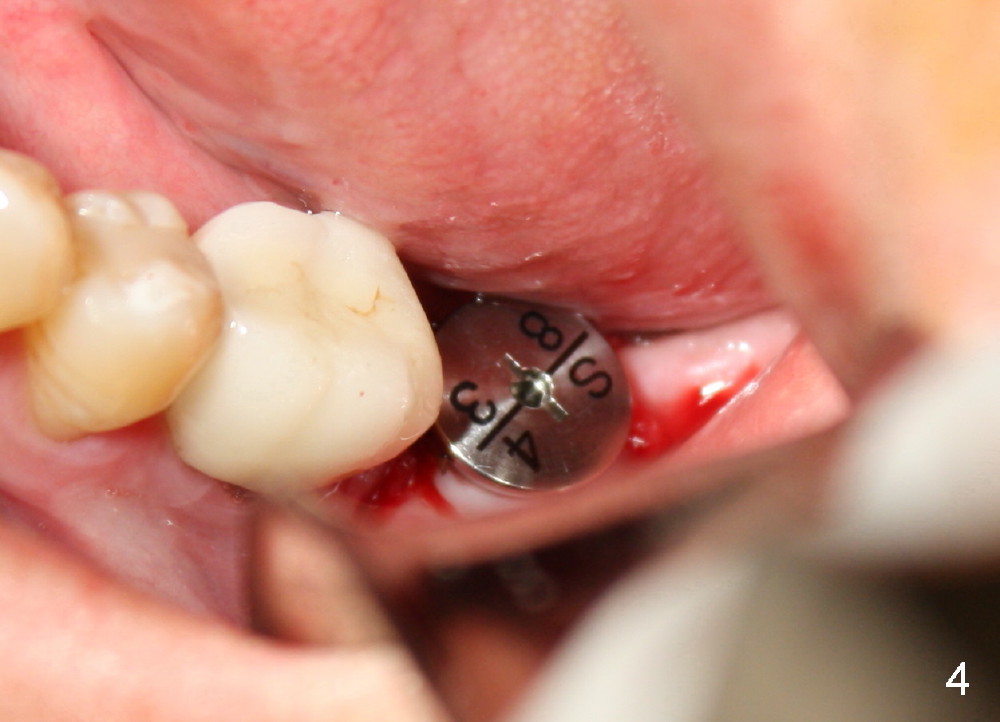

Approximately 1 mm coronal portion of the implant is exposed buccally and lingually. The exposed portion is covered by autogenous graft harvested during osteotomy and collagen membrane. The membrane is fixated between the implant and healing abutment (8.2(4(3)) (Fig.4). There are two unexpected advantages associated with using the healing abutment. The first is that the abutment reduces tension in suturing. The second is that perio dressing can be tucked underneath the hemisphere of the the large (8.2 mm) and tall (4 mm) abutment (Fig.5 ^). The dressing is more secure. It should not be dislodged in a week postop.